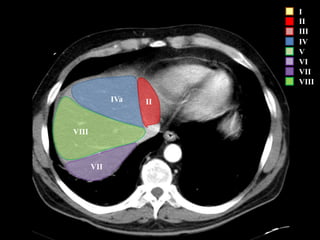

COUINAUD asignó un sistema de numeración para definir la segmentación

hepática.

I

II

III

IV

V

VI

VII

VIII

IVa

I – Entre cava y porta

II – el más superior de los izquierdos

III – Por debajo del II

IV – por delante de la vesícula

V – por detrás de la vesícula

VI – relación con riñón derecho

VII – el más posterior de los segmentos superiores

VIII – domo hepático

Las claves de la segm. Hepática